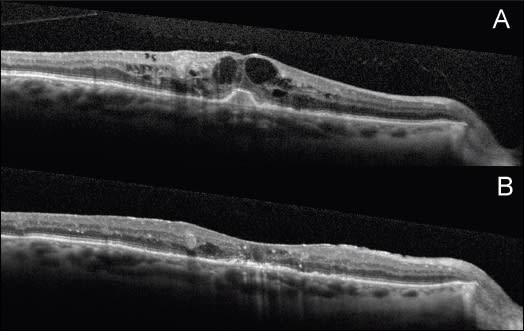

Figure 3. A. A baseline OCT linear scan shows a thickened posterior hyaloid, cystic macular edema, and bumped RPE in the fovea. B. A follow-up OCT linear scan three months after vitrectomy shows improvement of DME; however, the ELM is focally disrupted in the fovea, and the IS/OS junction is thickened.